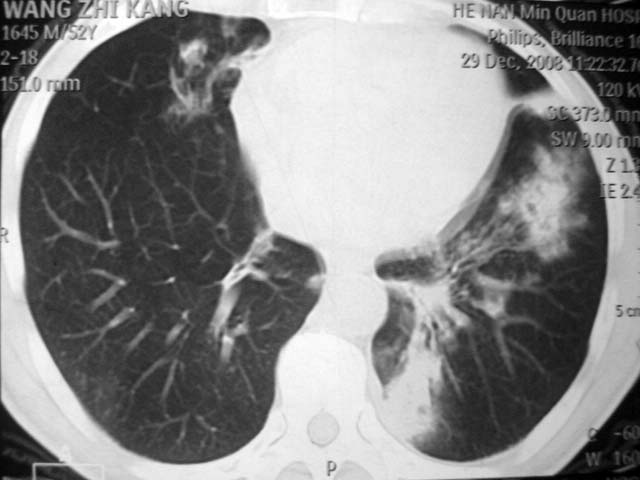

男,52岁,发热2月,糖尿病史。

抗结核治疗irpz方案,血糖未治疗,空腹15.9左右。症状无好转,左胸痛。

2、双肺见多发片状及结节状高密度影,大多数病灶中心均见“空泡征”。

结果:两肺继发性肺结核并曲霉菌感染。